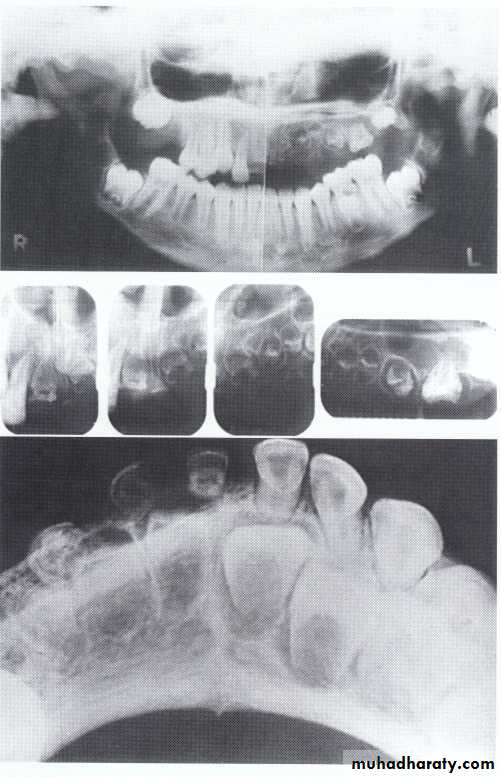

Hypodontia

Oligodontia

Anadontia

Developmental absence of all maxillary premolars and both mandibular second premolars. Note the retention of the maxillary primary canine as a result of the posterior position of the maxillary permanent canine.